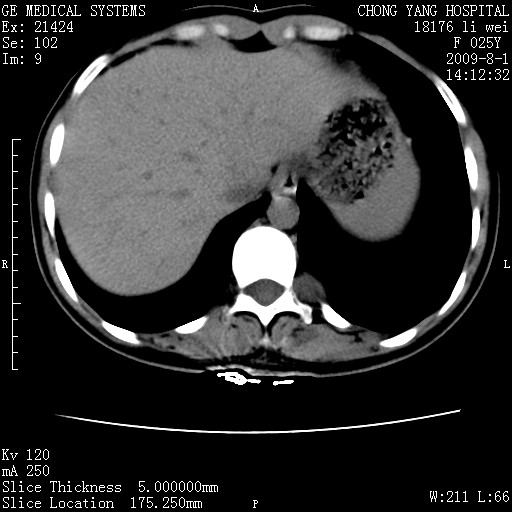

以下是引用pujunzhi在2009-8-1 20:23:00的发言:[br]胸椎旁及背部肌间良性病变,范围广,边界清,沿肌间生长,考虑淋巴管瘤、血管瘤,建议增强扫描。